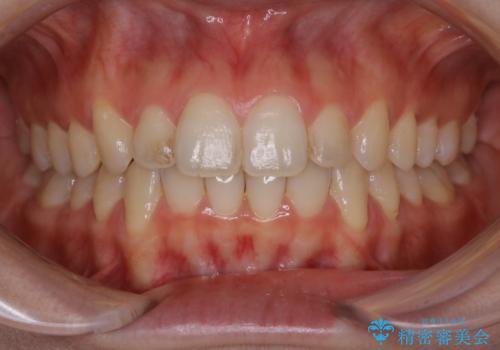

前歯の着色をPMTCできれいに

- 前歯に付着している着色がきになるとのことでした。PMTC30分コースを行いました。